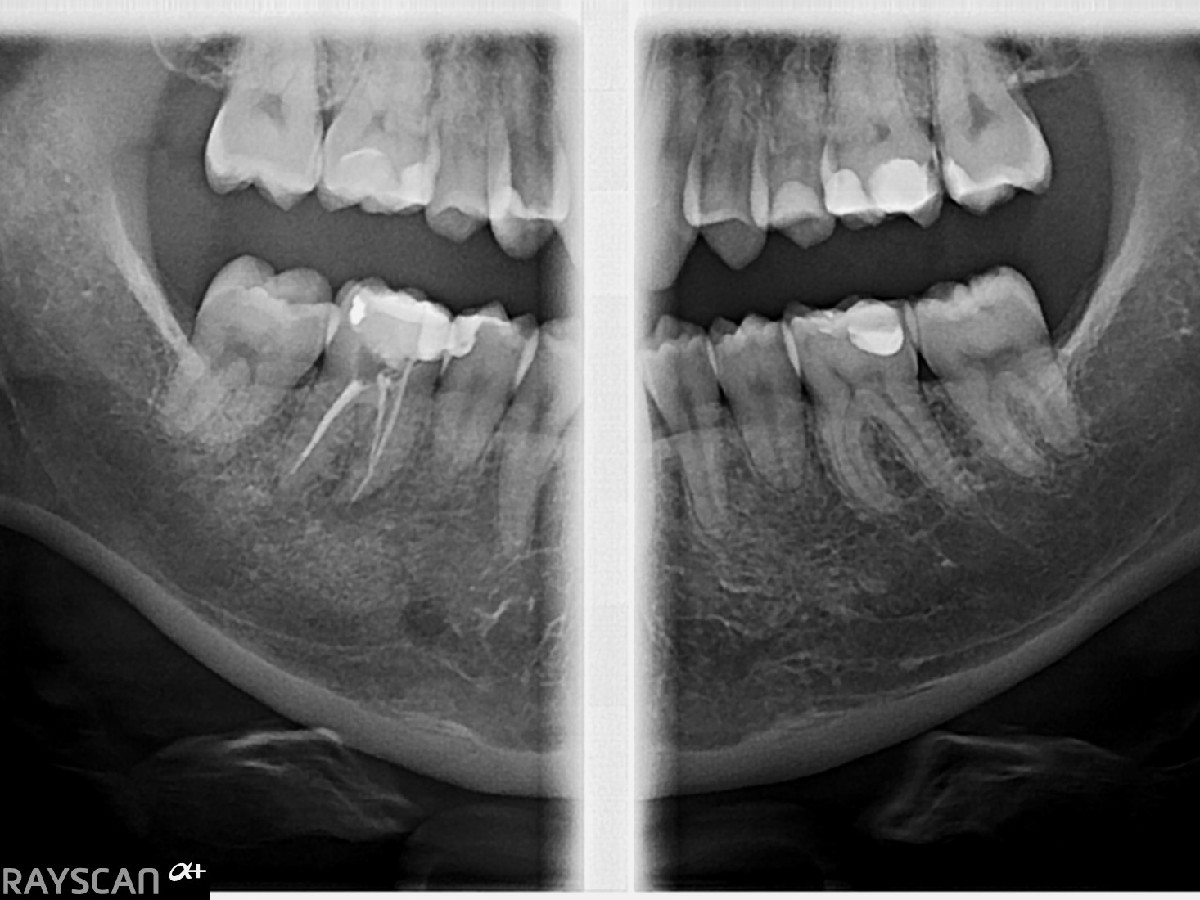

RTG skrzydłowo-zgryzowe prawe i lewe to specjalistyczne badanie rentgenowskie, które umożliwia jednoczesną ocenę koron zębów górnych i dolnych. Dzięki niemu można dokładnie przeanalizować stan uzębienia oraz wykryć ewentualne zmiany np. próchnicę, zwłaszcza w miejscach trudnych do zdiagnozowania podczas standardowego badania stomatologicznego. Zdjęcie to jest często stosowane w profilaktyce i diagnostyce stomatologicznej, pomagając w wykrywaniu niewidocznych gołym okiem problemów w obrębie jamy ustnej.

RTG skrzydłowo-zgryzowe to szybkie, bezbolesne i precyzyjne badanie, które pozwala wykryć próchnicę w trudno dostępnych miejscach. Obejmuje obie strony jamy ustnej, co pozwala na analizę symetrycznych struktur zgryzu. Dodatkowo znajduje zastosowanie w ocenie poziomu kości wyrostka zębodołowego, wspomagając diagnostykę chorób przyzębia.

Przygotowanie do prześwietlenia koron zębów górnych i dolnych jest bardzo proste. Przed wykonaniem zdjęcia zaleca się, aby pacjent usunął wszelkie metalowe przedmioty znajdujące się w okolicach głowy, takie jak biżuteria, okulary, spinki do włosów, a także inne akcesoria, które mogą zakłócić jakość uzyskiwanego obrazu rentgenowskiego. Ponadto przed badaniem nie ma konieczności stosowania żadnej specjalnej diety ani modyfikacji w zakresie przyjmowania leków.